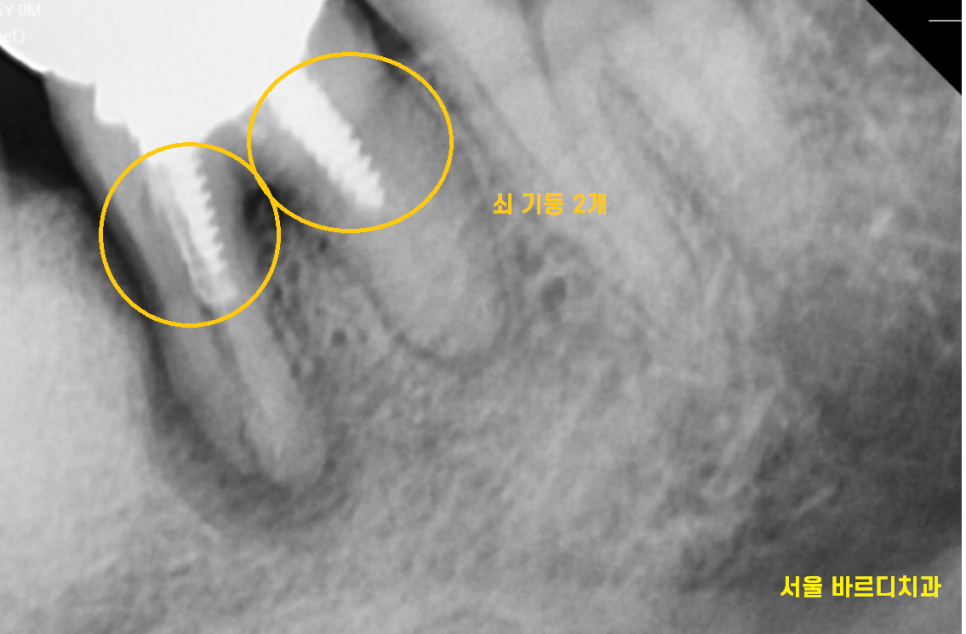

"환자분 혹시 치료할 때 딱딱한 음식 피하라고 들으시지 않으셨나요~?"

x-ray 사진을 보면서 다시 여쭤보았습니다.

왜냐면 치아가 남아있는 양이 별로 없을 때

기둥을 세워 보강하는데

2개나 있었거든요ㅠㅠ

그만큼 남아있는 치아의 양이 없다는 것으로

치아가 약했다는 것을 뜻합니다.